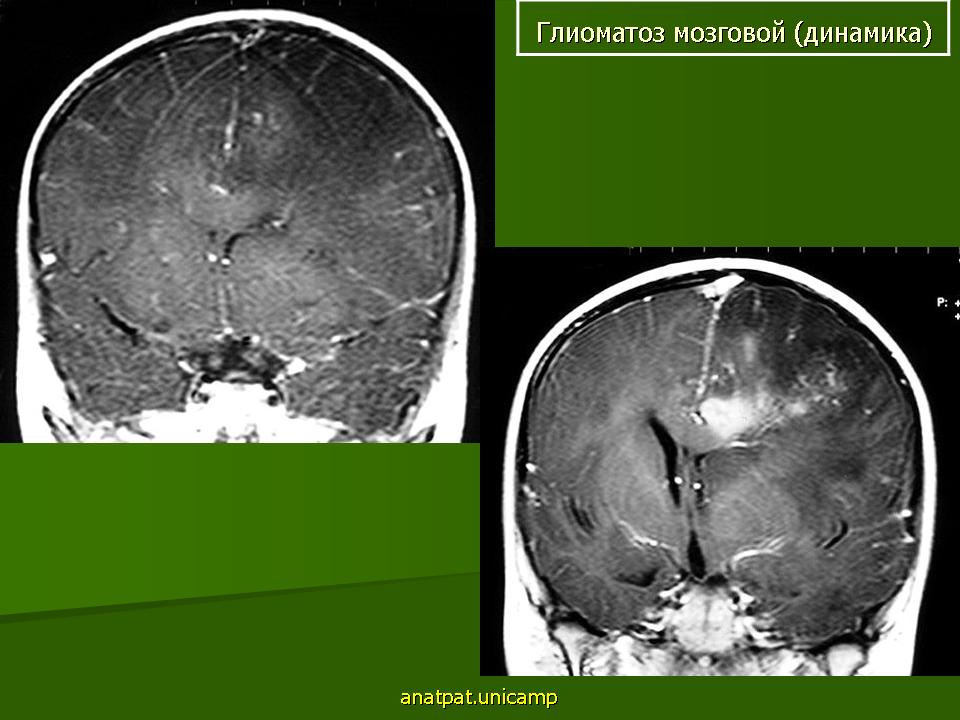

Глиоматоз мозговой. Ср, 03/09/2014 - 12:08 #1 Катенёв Валенти... Не на сайте Был на сайте: 7 лет 3 месяцев назад Зарегистрирован: 22.03.2008 - 22:15 Публикации: 54876 Продолжение.Приложения:

Продолжение.